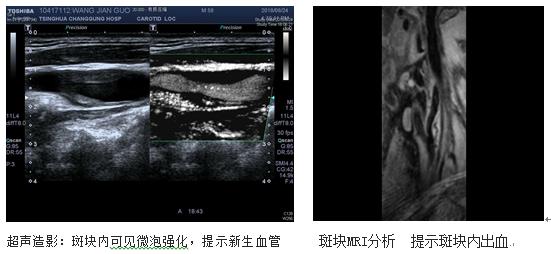

颈动脉彩超检查能够做出初步判断,但其受检查技师操作经验及主观判断影响大。为了进一步指导手术治疗,还需要明确颈动脉狭窄部位、长度以及程度、斑块成分等详细信息。颈动脉血管造影(DSA)能准确检查出动脉狭窄的程度和范围,而且能动态了解全脑动脉血流状况,是诊断头颈部动脉病变的金标准。近年来,应用超声造影、CT血管增强(CTA)以及磁共振斑块分析(MRI)等技术,同样可以得到全面的斑块信息,通过三维建模从不同的角度显示血管结构,良好地识别不稳定斑块。

如果斑块增大到一定程度,就要及时行斑块稳定性评估,如果超声造影提示:斑块内有大量新生血管形成,斑块纤维帽不完整;斑块高分辨核磁分析提示:斑块内出血及存在大的脂类核心、纤维帽破裂等情况,说明斑块极不稳定,脱落导致远端脑梗塞风险较大。